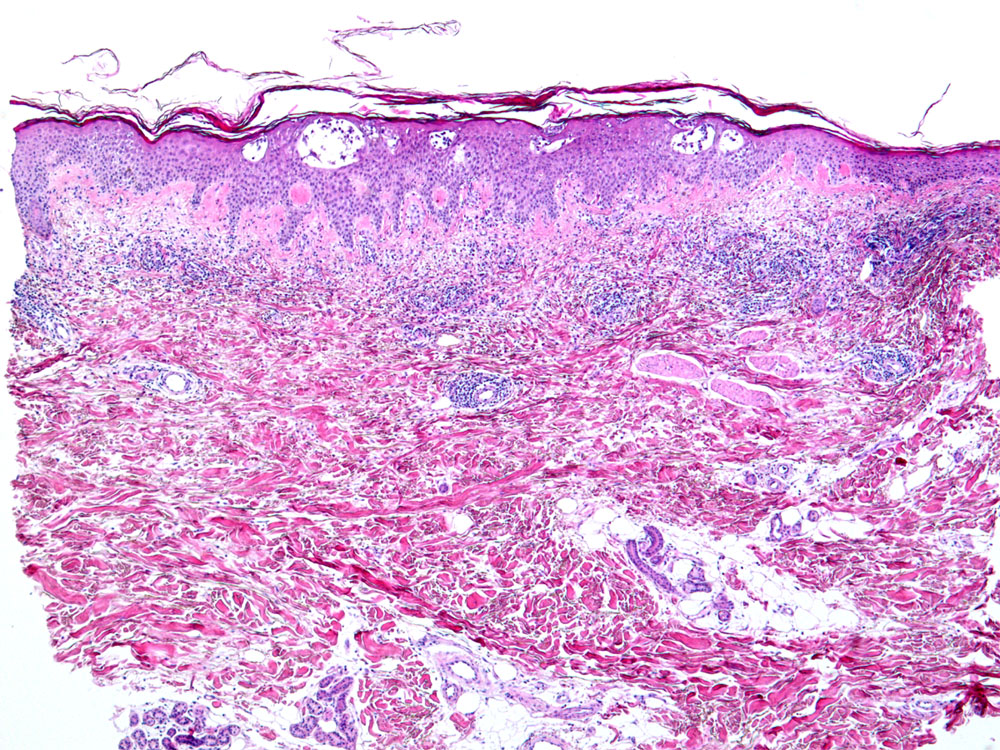

PathoPic – image database / PathoPic ID 10742 - Akute spongiotische Dermatitis vom Ekzemtyp

Akute spongiotische Dermatitis vom Ekzemtyp

Geringgradige irreguläre Akanthose der Epidermis. Epidermis und papilläre Dermis erscheinen aufgrund des Ödems relativ hell. Intraepidermale Spongiosebläschen. Schuppenkruste. Oberflächliches perivaskulär betontes Entzündungsinfiltrat.

Randbetonte Rötung mit Infiltration am linken Oberschenkel.

Morphologisch sind die allergische Kontaktdermatitis, das nummuläre Ekzem, die dyshidrotische Dermatitis und die Id Reaktion nicht unterscheidbar. Je nach Stadium unterschiedliche Morphologie.